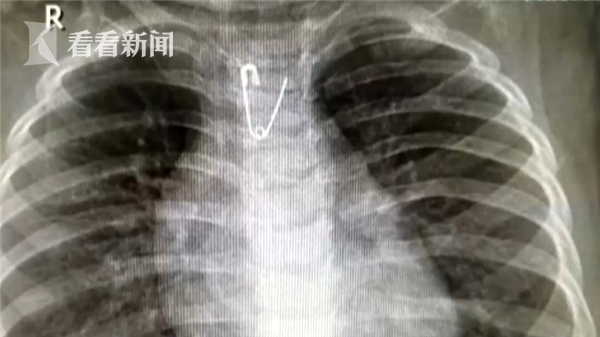

西安医学院第一附属医院儿科主治医师李伟琴说:“很快片子就回来 是一个金属的小别针,而且是开口的,在食管中段。”

由于别针比较尖锐,很有可能刺破食管,刺破主动脉,进而导致急性内脏大出血,医院立即组织多科室会诊,经过细致讨论,最终决定尝试为小宝行全麻下胃镜取异物术,通过胃镜观察,小宝的食管已经被别针刺破,有明显鲜血溢出。

手术很顺利,目前,小宝宝病情已经稳定,需留院观察几天便可出院。一个开口的别针倒挂在食管中段,比邻主动脉!意味着,如果再晚来一会,随时可能发生危险,而妈妈教科书式的做法,也救了自己的孩子。